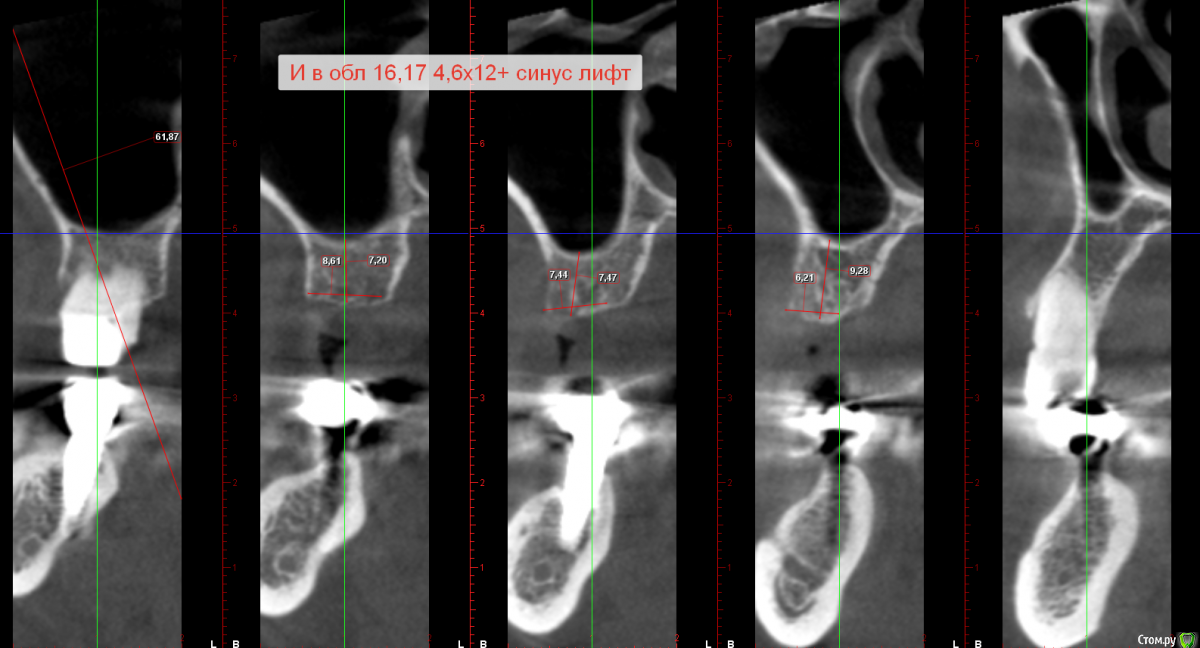

Sergiosse Опубликовано 19 августа, 2016 Поделиться Опубликовано 19 августа, 2016 Планируется установка двух имплантантов. Пациентка категорически отказывается от Открытого синуса, просит сделать все максимально бюджетно. Какую методику предпочесть бикортикальную фиксацию 8 мм. имплантанта или закрытый синус с 10мм имплантантом? Ссылка на комментарий

Nazim_NV86 Опубликовано 20 августа, 2016 Поделиться Опубликовано 20 августа, 2016 Ответ дан выше. Вот пример,недавно делал. 7-ка для премоляра, а 8,5 для моляра поставил. Ссылка на комментарий